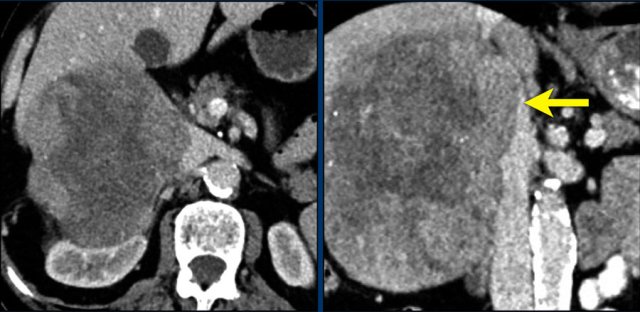

Axial and coronal CT images in a patients with a right adrenal carcinoma and extensive IVC invasion.

The coronal image also shows tumor extension into the right renal vein.

Axial and coronal CT images of another patient with an adrenal carcinoma with extensive IVC invasion (yellow arrow).

IVC and renal vein tumor invasion are seen in up to 20% of patients.